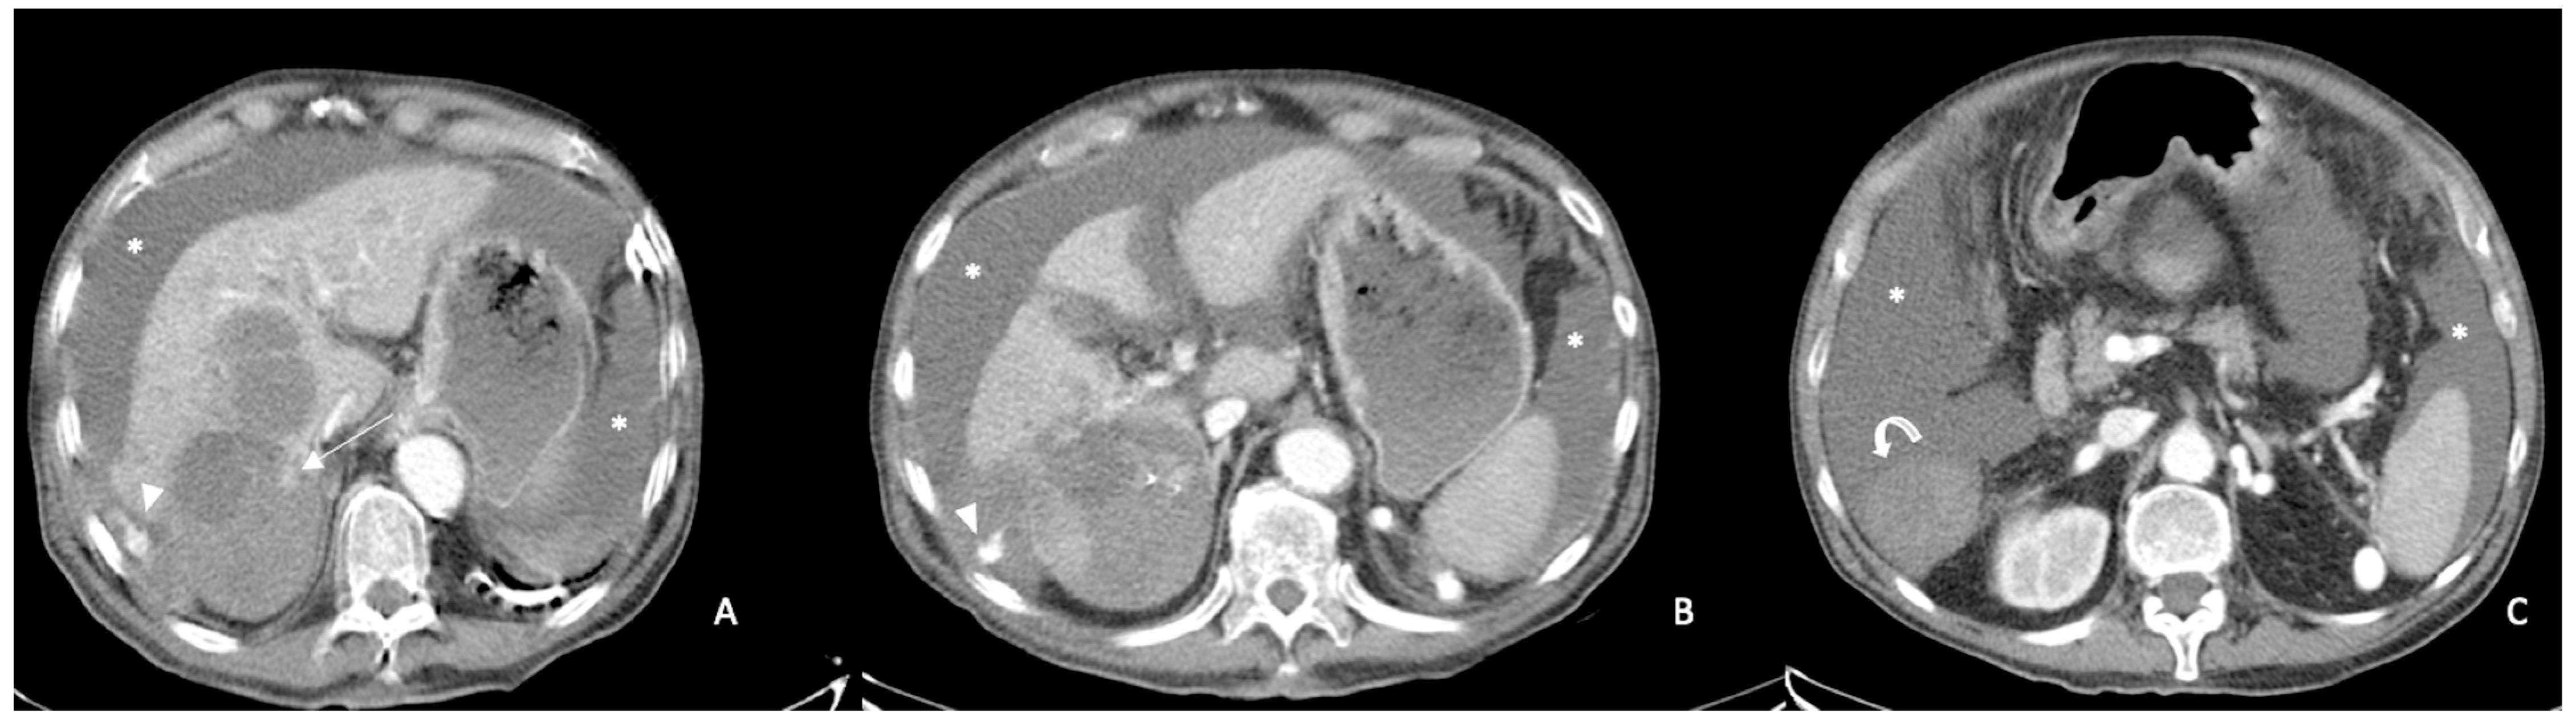

- Kim, H.C.; Yang, D.M.; Jin, W.; Park, S.J. The Various Manifestations of Ruptured Hepatocellular Carcinoma: CT Imaging Findings. Abdom. Imaging 2008, 33, 633–642. [Google Scholar] [CrossRef]

- Furlan, A.; Fakhran, S.; Federle, M.P. Spontaneous Abdominal Hemorrhage: Causes, CT Findings, and Clinical Implications. AJR Am. J. Roentgenol. 2009, 193, 1077–1087. [Google Scholar] [CrossRef] [PubMed]

- Ilyas, M.; Bashir, M.; Robbani, I.; Rasool, S.R.; Shera, F.A.; Hamid, I. Sentinel Clot Sign in Hemoperitoneum. Abdom. Radiol. 2019, 44, 1955–1956. [Google Scholar] [CrossRef]

- Orwig, D.; Federle, M.P. Localized Clotted Blood as Evidence of Visceral Trauma on CT: The Sentinel Clot Sign. AJR Am. J. Roentgenol. 1989, 153, 747–749. [Google Scholar] [CrossRef]

- Singhal, M.; Sinha, U.; Kalra, N.; Duseja, A.; Khandelwal, N. Enucleation Sign: A Computed Tomographic Appearance of Ruptured Hepatocellular Carcinoma. J. Clin. Exp. Hepatol. 2016, 6, 335–336. [Google Scholar] [CrossRef]